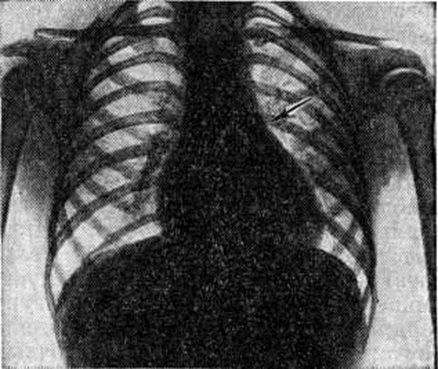

Диагноз. При аортальном стенозе данные векторкардиографии (смотри полный свод знаний) отражают подъём левожелудочкового давления лучше, чем ЭКГ. Только заметное повышение давления (градиент давления на уровне сужения более 60 миллиметров ртутного столба) приводит к появлению на ЭКГ признаков гипертрофии левого желудочка. У новорождённых на ЭКГ могут быть лишь признаки гипертрофии правого желудочка. Характерные клинические, симптомы в сочетании с признаками гипертрофии левого желудочка на ЭКГ указывают на выраженный аортальный стеноз (рисунок 3). При рентгенологическое исследовании у детей тень сердца нормальных размеров или с признаками гипертрофии левого желудочка. При высоком конечно-диастолическом давлении в левом желудочке и левом предсердии отмечаются застойные явления в прикорневых отделах лёгких. Может быть расширена восходящая часть аорты (постстенотическая дилатация). У детей с выраженным стенозом рентгенологически определяется аортальная конфигурация сердца (рисунок 4) и усиленный легочно-сосудистый рисунок. При ретроградной катетеризации сердца катетер проводят через место сужения в полость левого желудочка, измеряют градиент давления, выявляют место сужения и возможные сопутствующие пороки. У новорождённых и грудных детей катетеризация сердца может быть заменена эхокардиографическим исследованием (смотри полный свод знаний: Эхокардиография). У больных с асимметричной перегородочной гипертрофией во время систолы происходит смыкание передней створки левого предсердножелудочкового (митрального) клапана с гипертрофированным миокардом. Сужение может сопровождаться большим градиентом давления. При нагрузках, приёме сердечных гликозидов или инотропных средств и нитроглицерина градиент давления возрастает, но снижается при использовании р-адреноблокаторов (анаприлина, обзидана, индерала). Во время систолы, следующей после экстрасистолы, артериальное давление уменьшается, в то время как при других видах аортальногостеноза оно возрастает. При массивной мышечной гипертрофии возникает обструкция выходного отдела левого желудочка, нарушается функция митрального клапана. Признаки заболевания аналогичны таковым при других видах аортального стеноза, однако на ЭКГ всегда регистрируют выраженную гипертрофию левого желудочка, удлинение интервала Q — Г, изменения S — Г, зубцов Т и Q. Диагноз может быть установлен достаточно точно с помощью эхокардиографии. Во время катетеризации сердца на киноангиокардиограмме (смотри полный свод знаний: Ангиокардиография) в боковой проекции видно сужение полости левого желудочка в его выходной части. Детей с сердечной недостаточностью оперируют по жизненным показаниям. Так называемый плановые операции при аортальном стенозе выполняют, если в покое градиент давления на уровне сужения выше 60 миллиметров ртутного столба. Аортальную вальвулотомию производят либо по закрытой методике (через верхушку сердца в аорту последовательно проводят вальвулотом и дилататор), либо на «открытом» сердце в условиях умеренной гипотермии (общей или краниоцеребральной) при пережатых полых венах. Доступ — через стенку аорты. В течение 3—5 минут рассекают клапан по комиссурам. Безопаснее устранять порок в условиях искусственного кровообращения. Наибольшие трудности возникают при коррекции надклапанного сужения с гипоплазией аорты, что требует вшивания заплаты в стенку аорты, иногда с протезированием клапанов сердца (смотри полный свод знаний), и асимметричной гипертрофии миокарда. Иссечение мышечных масс может быть выполнено из аортального доступа, который иногда приходится дополнять рассечением стенки левого желудочка. Существуют методики, предусматривающие иссечение миокарда со стороны правого желудочка. К более радикальным операциям относится иссечение миокарда через левое предсердно-желудочковое отверстие с последующим протезированием митрального клапана. Ок. 10% неоперированных детей раннего возраста имеют явные признаки левожелудочковой недостаточности. В течение первого года жизни (особенно первого месяца) большая их часть погибает. У выживших со средней степенью сужения клинические, признаки Пороки сердца врождённые с возрастом нарастают. Страдающие тяжёлой формой стеноза в 1—7% случаев умирают внезапно. В 20% случаев при стенозе развивается регургитация. При асимметричной гипертрофии перегородки сердца продолжительность жизни ограничена 40—50 годами. Результаты оперативного лечения во многом определяются исходной степенью тяжести стеноза, его морфологией, состоянием миокарда левого желудочка, радикальностью оперативного вмешательства и отсутствием послеоперационной недостаточности клапана. Операционная летальность не превышает 10%. Через 10 лет около 25% оперированных нуждается в повторном вмешательстве для ликвидации рестеноза или регургитации. Во время повторных операций, как правило, производят протезирование клапана. У остальных отдалённые результаты хорошие и удовлетворительные: большая часть из них может считаться практически здоровыми. Аортолёгочный свищ — врождённое соустье между восходящей частью аорты и лёгочным стволом — относится к редким аномалиям (0,3% всех врождённых пороков «сердца.). На 8-й неделе у эмбриона формируется спиральная перегородка, которая при нормальном развитии делит общий артериальный ствол на два продольных канала (аорту и лёгочный ствол) и срастается в области их фиброзных колец с межжелудочковой перегородкой. Нарушения механизма образования перегородки приводят к появлению патологический отверстия между двумя магистральными сосудами. В большинстве случаев дефект располагается на 1—5 миллиметров выше фиброзного кольца устья аорты. Реже отверстие достигает клапанов аорты и лишь иногда располагается в дистальной х/3 восходящей части аорты. Размеры соустья варьируют широко — от 2 до 30 миллиметров. Отсутствие межсосудистой перегородки от клапанов аорты до дистального отдела восходящей части аорты может рассматриваться как общий артериальный ствол. Характер гемодинамических нарушений при аортолёгочном свище во многом сходен с расстройствами кровообращения при открытом артериальном протоке. Однако вследствие близости патологический отверстия к устью аорты (отверстие аорты) осложнения развиваются быстрее, в частности лёгочная гипертензия. Клиническая картина определяется размерами аортолёгочного свища и состоянием сосудов лёгких. При небольших размерах свища (менее 5 миллиметров) течение порока аналогично таковому при артериальном протоке. Однако эпицентр систолодиастолического шума при этом пороке располагается ближе к средней линии во втором межреберье у грудины. При средних размерах свища (6—10 миллиметров) клинические, проявления более тяжёлые, чем при артериальном протоке такого же диаметра. Отмечается бледность, ребёнок отстаёт в физическом развитии, у него легко возникает одышка, даже при небольших физических нагрузках; характерны слабость, повышенная утомляемость. Большой свищ (более 10 миллиметров) сопровождается высокой лёгочной гипертензией, поэтому возникновение цианоза, приступов одышки, нарушений ритма (вначале лишь при нагрузках) свидетельствует о выравнивании давления в аорте и лёгочном стволе и двустороннем шунтировании крови. В этот период может проявиться сердечная недостаточность. До развития лёгочной гипертензии (при малых и средних размерах свища) клинические, признаки порока во многом совпадают с проявлениями артериального протока (систолодиастолический шум, дрожание над сердцем и другие). При развитии лёгочной гипертензии вначале исчезает диастолический шум, а затем ослабевает и систолический. На ЭКГ в зависимости от степени нарушений гемодинамики определяются признаки перегрузки левого, обоих или преимущественно правого желудочка, нарушения сердечного ритма (пароксизмальная тахикардия, экстрасистолия). При рентгенологическое исследовании — изменения размеров сердца и сосудов лёгких взаимосвязаны с величиной и направлением сброса крови. При большом артериовенозном сбросе увеличены основание и левые отделы сердца, усилен лёгочный рисунок, выбухает дуга лёгочного ствола; при сбалансированном шунте наблюдается гипертрофия обоих желудочков, обеднение сосудистого рисунка по периферии лёгких. Катетеризация и контрастирование сердца являются основными методами распознавания порока и установления степени нарушений гемодинамики. Катетер, проведённый из правого желудочка в лёгочный ствол, может попасть через свищ в аорту. В зависимости от величины давления в аорте и лёгочном стволе контрастирование одной из них может дать полное представление о локализации, размерах, направлении и объёме шунта. Для этой цели производят аортографию (смотри полный свод знаний) в прямой и правой косой позиции (с помощью катетера, проведённого ретроградно до клапана аорты). Величина сброса крови может быть установлена также исследованием её на насыщение кислородом в различных участках правых отделов сердца и лёгочном стволе красочными, платиноводородными и термодилюционными пробами. Порок следует дифференцировать с открытым артериальным протоком (смотри полный свод знаний), дефектом межжелудочковой перегородки, стенозом лёгочной артерии, стенозом устья аорты, недостаточностью митрального клапана, разрывом аневризмы синуса Вальсальвы, аневризмами коронарных сосудов, артериовенозными аневризмам левой внутригрудной, межрёберных артерий или перикардиальных сосудов. Лечение оперативное, за исключением больных с выраженной лёгочной гипертензией и преобладающим венозно-артериальным сбросом крови (им показано ограничение в физических нагрузках и терапия сердечной недостаточности). Для закрытия свища существует несколько способов. Свищ, расположенный выше аорты и клапанов лёгочного ствола, перевязывают несколькими лигатурами. Если свищ прилегает к клапану аорты, то его можно ушить со стороны лёгочного ствола (рисунок 5) в условиях умеренной гипотермии с выключением сердца из кровообращения. В большинстве же случаев операция при аортолёгочном свище проводится в условиях искусственного кровообращения. В зависимости от размеров отверстия и продолжительности операции применяется один из видов защиты миокарда (холодовая или медикаментозная кардиоплегия, коронарная перфузия и тому подобное). При дистально пережатых сосудах производят либо ушивание свища, либо вшивание заплаты (что предпочтительно) со стороны аорты или лёгочного ствола. Неоперированные больные с лёгочной гипертензией обычно погибают в детском возрасте. Летальность после операций у больных без выраженной лёгочной гипертензии не превышает 5%, у больных с лёгочной гипертензией более 50%. Результаты в отдалённые сроки после операции в подавляющем большинстве случаев благоприятные. Артериальный проток соединяет аорту с лёгочным стволом. Необходимый в период эмбрионального развития для нормального кровообращения, после рождения ребёнка он облитерируется. Если облитерация не наступает, развиваются нарушения гемодинамики, сброс крови из аорты в лёгочный ствол. Лечение оперативное (смотри полный свод знаний: Артериальный проток). Атрезия лёгочного ствола в сочетании с дефектом межжелудочковой перегородки представляет собой одну из форм тетрады Фалло. Обычно наблюдается гипоплазия правого желудочка (I тип); возможно сочетание нормального или даже расширенного правого желудочка с несостоятельностью трёхстворчатого клапана (II тип). Клапан лёгочного ствола маленький, заращён. Дистальнее его ствол сосуда сохранен. Центральный кровоток осуществляется через дефект перегородки в левые отделы сердца и аорту, далее через артериальный проток в сосуды лёгких. Артериальный проток обычно узкий. Степень цианоза зависит от величины сброса крови через артериальный проток. Цианоз заметен с момента рождения, усиливается с развитием сердечной недостаточности; наблюдаются приступы гипоксии, ацидоз. На ЭКГ отмечаются признаки преобладания левого желудочка, особенно при I типе порока. Рентгенологические исследование выявляет увеличение размеров сердца, лёгочно-сосудистый рисунок ослаблен. При контрастировании сердца виден правый желудочек с выходным отделом в виде слепого мешка и регургитацией в предсердие. Этот порок нужно дифференцировать с трикуспидальной атрезией, тетрадой Фалло, стенозом лёгочного ствола, транспозицией крупных сосудов со стенозом лёгочного ствола. Лечение оперативное. Если правый желудочек недоразвит, то целесообразно наложить межсосудистый анастомоз; если он развит нормально, то производят лёгочную вальвулотомию. В некоторых случаях между правым желудочком и лёгочным стволом вшивают кондуит (консервированный в глутаровом альдегиде биологический трансплантат клапана сердца, вшитый в сосудистый протез). Послеоперационная летальность у новорождённых с гипоплазированным правым желудочком высокая (до 80%). Без операции практически все дети погибают в течение первого года жизни. Атрезия устья аорты сочетается с гипоплазией восходящей части аорты, гипоплазией или атрезией левого желудочка и атрезией или выраженным стенозом митрального клапана. Устья коронарных артерий, как правило, располагаются в луковице аорты. Для поддержания жизни необходимы артериальный проток и дефект межпредсердной перегородки (открытое овальное окно). Кровообращение при этом происходит следующим образом: венозная кровь большого и малого круга кровообращения смешивается в предсердии, поступает в правый желудочек, лёгочный ствол и через артериальный проток в аорту. Аортальная атрезия и другие варианты гипоплазии левых отделов сердца являются самой частой причиной смерти новорождённых с Пороки сердца врождённые Хотя при рождении ребёнок может выглядеть нормально, вскоре выявляется сердечная недостаточность с дилатацией правого желудочка, падением АД и цианозом. Данные физикального, электрокардиографического и рентгенологическое исследований далеко не всегда позволяют правильно распознать порок. Только эхокардиография, катетеризация сердца и киноангиокардиография дают возможность поставить окончательный диагноз и оценить гемодинамические нарушения. Порок считается неизлечимым, оперативное вмешательство не проводится. Большая часть новорождённых с этой патологией погибает в течение нескольких дней после рождения. Атриовентрикулярный канал (неполная форма) представляет собой сочетание первичного дефекта межпредсердной перегородки с расщеплением створки митрального или трёхстворчатого клапана или створок обоих клапанов. Первичный дефект межпредсердной перегородки всегда большой, имеет полулунную форму, сверху отграничен межпредсердной перегородкой, снизу фиброзным кольцом клапанов. Передняя створка митрального клапана расщеплена обычно в середине общей части фиброзного кольца клапана. Аналогично может быть изменена и перегородочная створка трёхстворчатого клапана.. Нарушения гемодинамики аналогичны таковым при первичном дефекте межпредсердной перегородки. Расщепление створки клапана приводит к регургитации крови из желудочка (или обоих желудочков) в оба предсердия; степень регургитации может быть различной. Для детей в возрасте до 3 лет при этом пороке характерна сердечная недостаточность, которая сопровождается одышкой, низкой толерантностью к физическим нагрузкам, резким отставанием в развитии ребёнка. У взрослых, как правило, наблюдаются хронический недостаточность кровообращения, приступы пароксизмальной тахикардии, присоединяется инфекционные эндокардит. Основные физикальные признаки порока: бледность кожи, «сердечный горб», интенсивный систолический шум над верхушкой сердца, расщепленный 11 тон над лёгочным стволом. На ЭКГ выявляются неполная блокада правой ножки пучка Гиса, отклонение электрической оси влево при наличии диастолической перегрузки правого желудочка; на ФКГ — интенсивный систолический шум над верхушкой сердца, расщепление II тона с усилением лёгочного компонента. Рентгенологически отмечается увеличение обоих желудочков, нередко кардиомегалия. При катетеризации сердца обнаруживают низкий дефект межпредсердной перегородки и регургитацию из желудочка при заполнении его контрастным веществом. Лечение — оперативное: из правосторонней торакотомии (смотри полный свод знаний) или срединной стернотомии (смотри полный свод знаний: Медиастинотомия) в условиях искусственного кровообращения расщепленную створку клапана соединяют отдельными П-образными швами, стремясь не сузить клапан. Дефект межпредсердной перегородки закрывают заплатой.